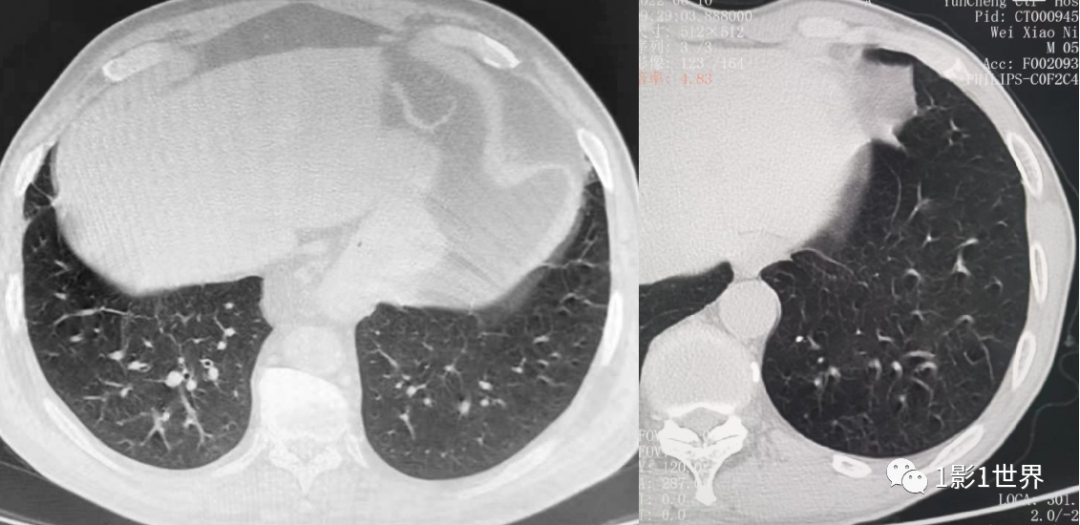

左下肺运动伪影,因呼吸控制不好,而出现的类似支气管扩张

的运动伪影